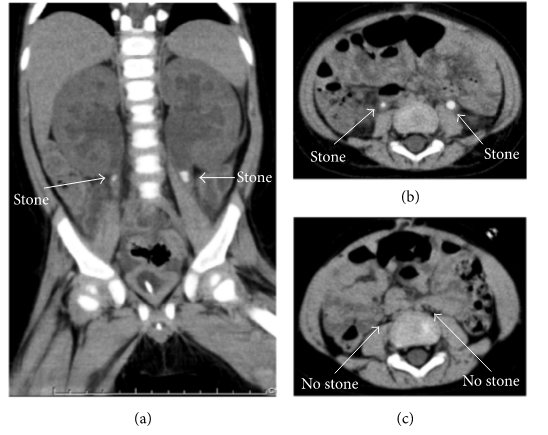

病例3. 患儿,男,15个月,严重腹泻及呕吐5天,因无尿和急性肾功能衰竭收住我院。USG和CT显示双侧轻度肾积水和输尿管结石(图1a和b),指示双侧输尿管梗阻及尿路结石导致肾功能衰竭。同上两例患者的处理方案一样,在全麻下插入经皮右肾穿刺造瘘管。经水合及尿碱化处理后,患儿于第1天通过肾造瘘管排除沙质结石。肾造瘘管插入10天后,右侧经皮顺行肾盂造影术显示由输尿管结石引起的梗阻正在消失并移除肾造瘘管。3个月后,CT扫描未发现结石(图1 c)。